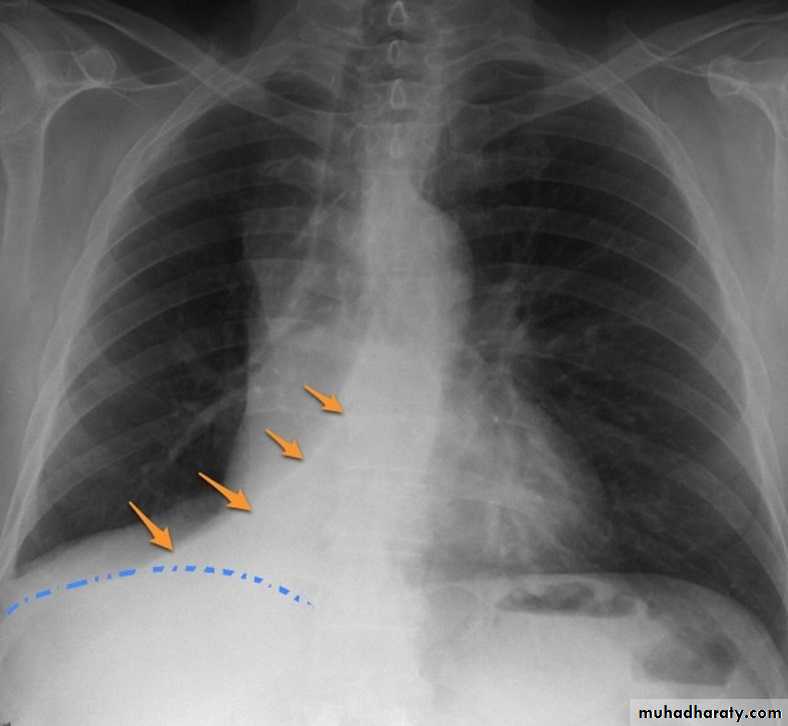

Right upper lobe collapse has distinctive features, and is usually easily identified on frontal chest radiographs .

Radiographic features

Chest radiograph

Collapse of the right upper lobe is usually relatively easy to identify on frontal radiographs. Features consist of :

increased density in the upper medial aspect of the right hemithorax

elevation of the horizontal fissure

loss of the normal right medial cardiomediastinal contour

elevation of the right hilum

hyperinflation of the right middle and lower lobe result in increased translucency of the mid and lower parts of the right lung

right juxtaphrenic peak

A common cause of lobar collapse is a hilar mass. When a right hilar mass is combined with collapse of the right upper lobe, the result is an S shape to elevated horizontal fissure. This is known as Golden S sign .